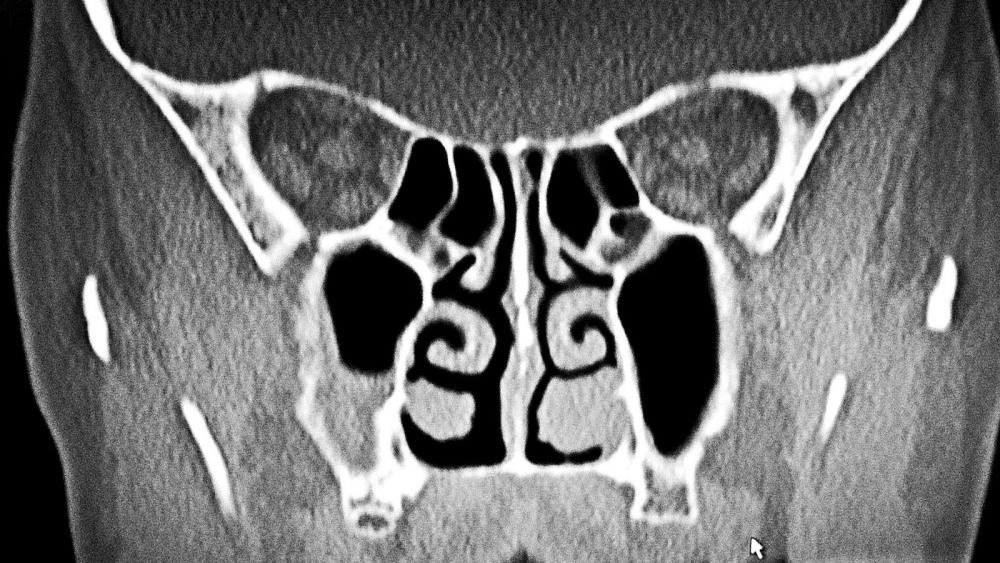

Diagnosis may involve visualization through otoscopic exam or behind the soft palate but usually needs radiographic evidence or more advanced imaging such as ct or. Nasal polyps are benign fleshy growths that develop in the nasal passages of cats. A nasopharyngeal polyp is a common non cancerous growth in the middle ear. Polyps in the back of your cats throat could cause snoring difficulty breathing and problems swallowing.